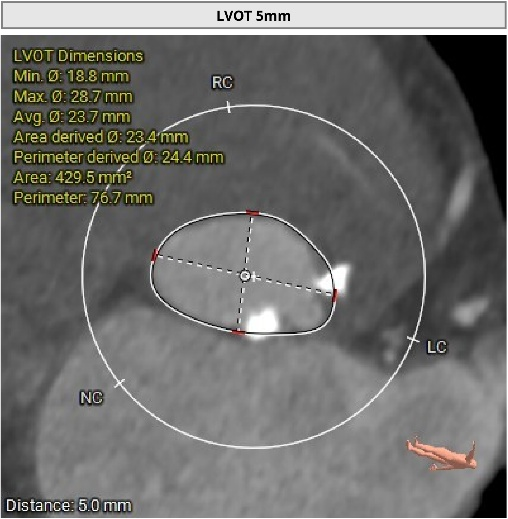

术前CT评估显示,患者瓣膜解剖条件总体具备经导管治疗基础,双侧冠脉阻塞风险偏低。

但与此同时,CT也提示患者存在冠状动脉三支严重钙化病变。也就是说,除了主动脉瓣问题外,供应心脏本身的血管也已经出现明显病变。如果不先处理冠脉问题,后续瓣膜治疗中的风险会进一步上升。

CT评估

瓣膜评估

进一步评估显示,患者瓣膜狭窄程度重,瓣叶钙化明显,左心室腔径偏小,手术中对器械通过、瓣膜释放以及循环稳定性的要求都更高。团队结合术前影像和整体身体状况,制定了周密的介入治疗方案,并做好相关风险预案。